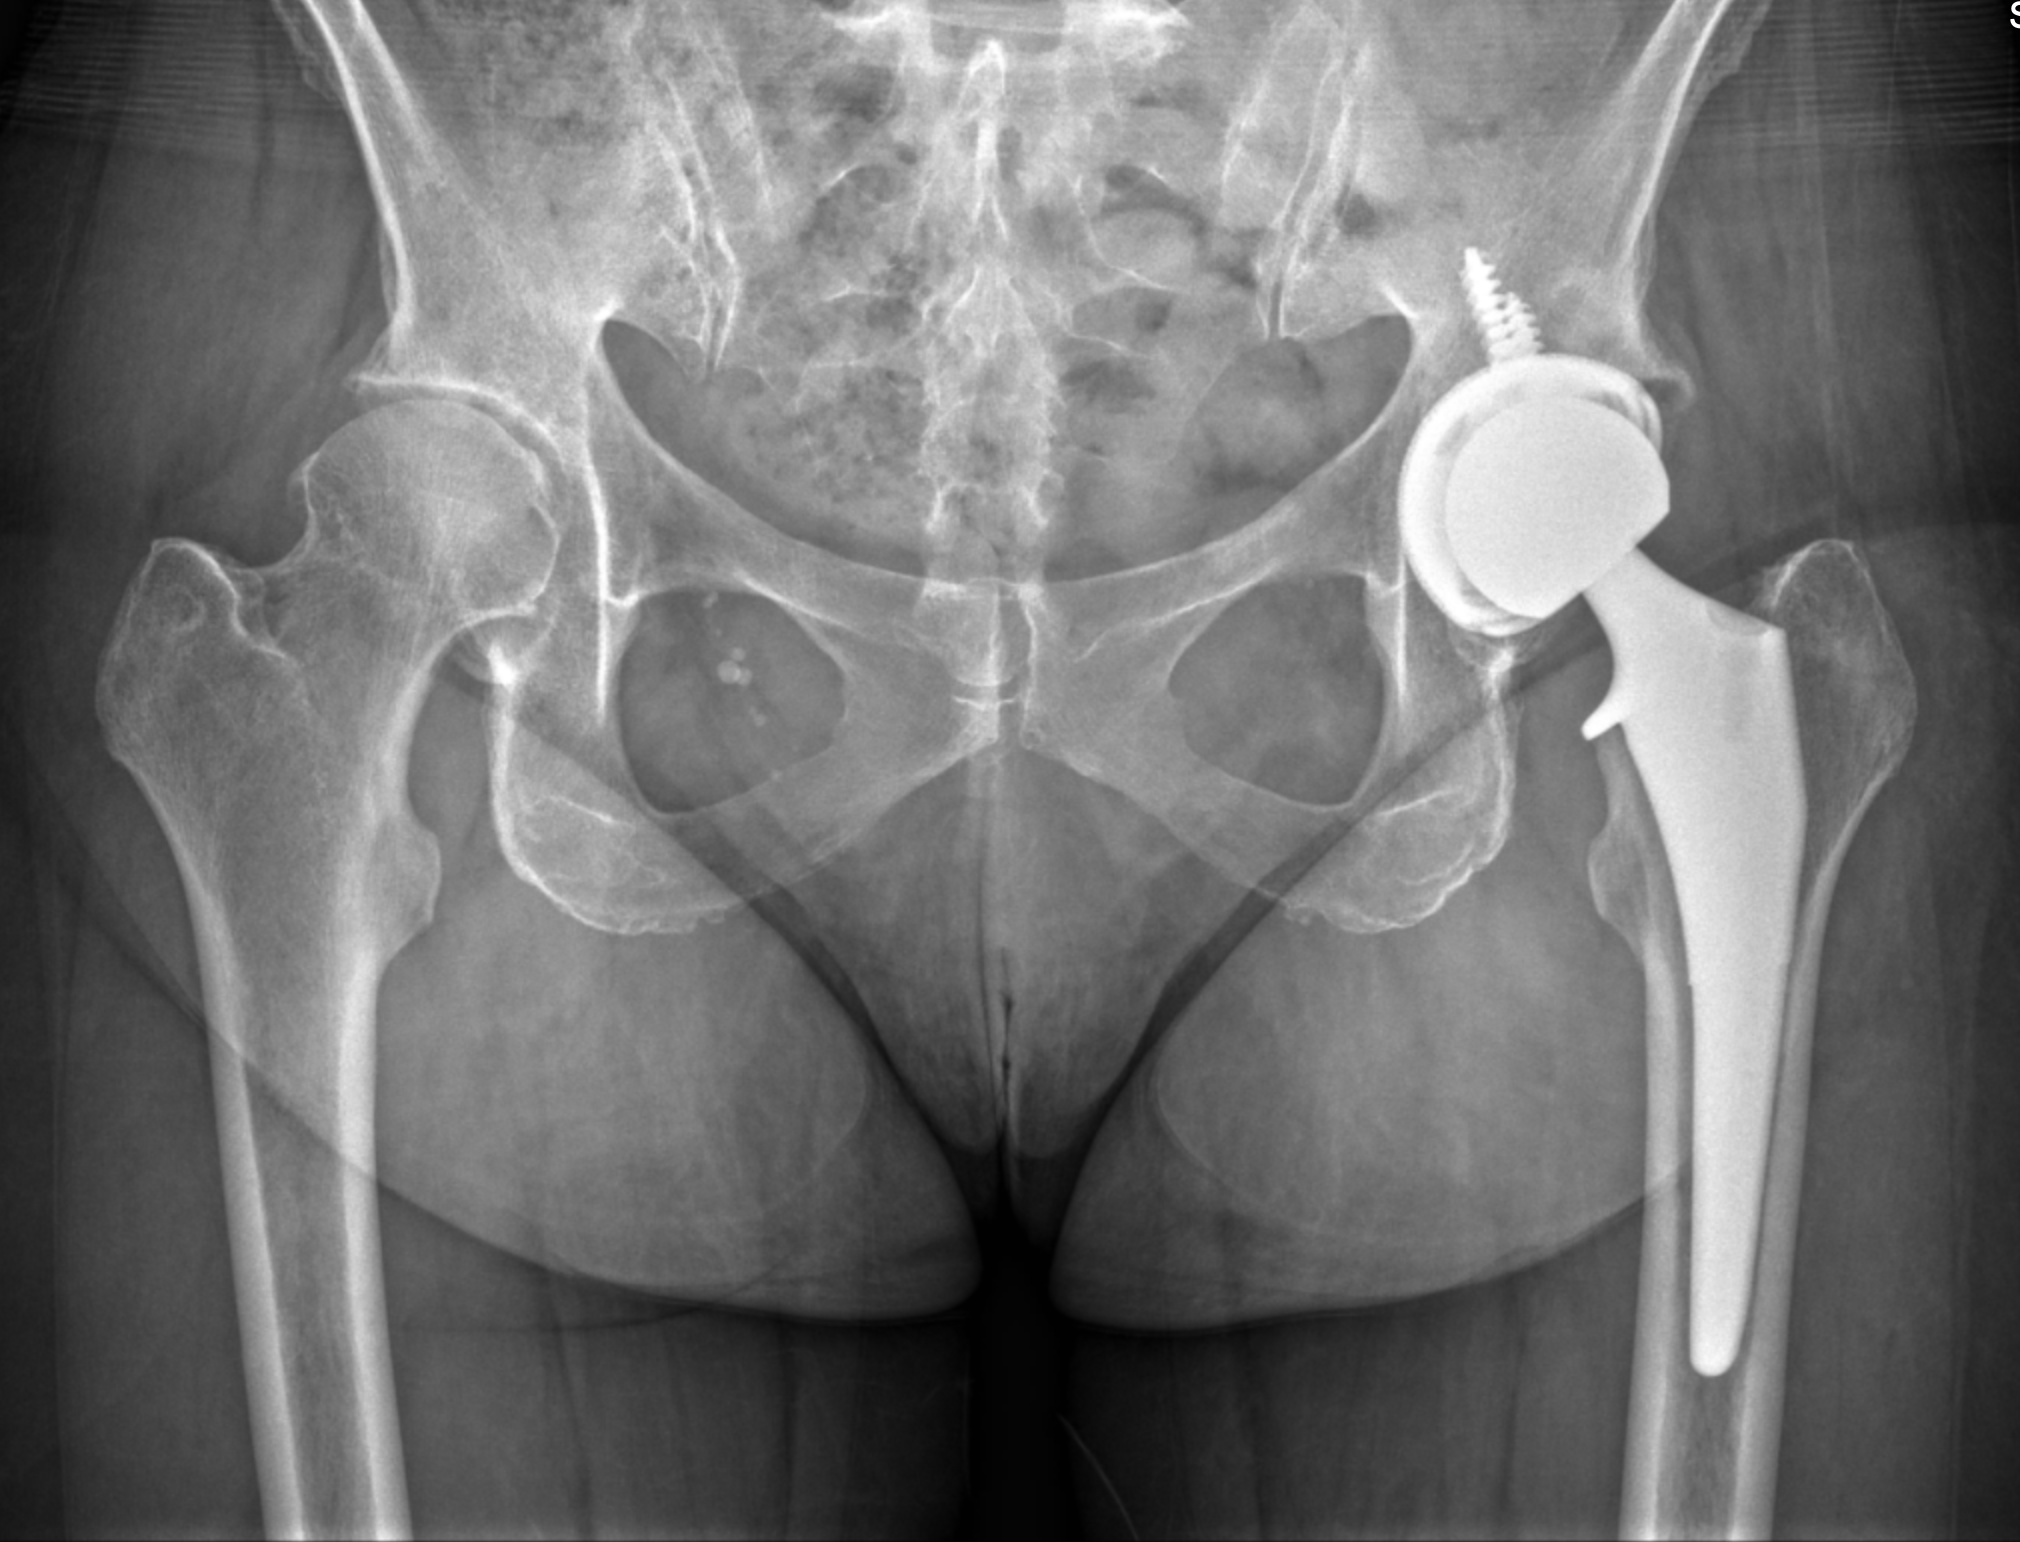

Dr. Kamran Movassaghi is a joint replacement specialist known for his precision, compassion, and modern approach to orthopedic care. With fellowship training in robotic and minimally invasive surgery, he helps patients regain mobility and freedom from joint pain.

Dr. Movassaghi uses MAKO SmartRobotics™ to deliver customized knee replacements with exceptional accuracy. This advanced system allows him to plan every detail before surgery and make precise adjustments during the procedure—helping patients experience less pain, better mobility, and a quicker recovery.